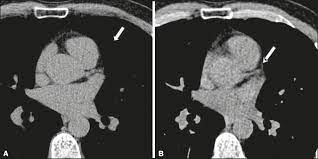

Heavily calcified stenosis of the mid-right coronary artery at baseline A and after percutaneous coronary intervention with RA 125 and 15mm burrs and drug-eluting stent implantation B. The presence of calcium in coronary arteries is almost always indicative of atherosclerotic plaque but bears no relationship to plaque stability or instability. Atheroma calcification is a common feature of advanced atherosclerosis however with the advent of CT scanning it has become possible to detect extensive coronary calcification in the absence of flow-limiting lesions.

People with coronary artery disease will have calcification of the blood vessels. Other components of the novel. Atheroma calcification is a common feature of advanced atherosclerosis however with the advent of CT scanning it has become possible to detect extensive coronary calcification in the absence of flow-limiting lesions. Researchers suggest that 90 of. Heavily calcified stenosis of the mid-right coronary artery at baseline A and after percutaneous coronary intervention with RA 125 and 15mm burrs and drug-eluting stent implantation B. The coronary artery calcium score is considered the most useful marker for predicting coronary events. There was no ECG gating. Coronary artery calcification pathologically begins as microcalcifications 05 to 150 μm and grows into larger calcium fragments which eventually result in sheet-like deposits 3 mm. Cardiac risk factors and insulin resistance lead to progression of coronary artery calcification.